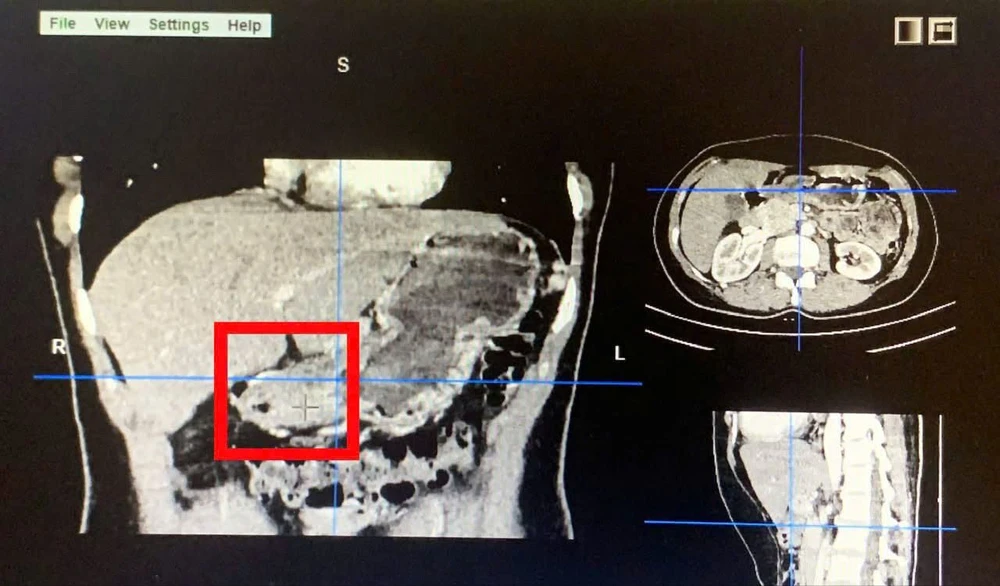

Khối u trên phim CT bụng. Ảnh: BVCC

Qua nội soi dạ dày, các bác sĩ phát hiện tổn thương ổ loét lớn bờ sượng cứng vùng bờ cong nhỏ - hang vị dạ dày. Kết quả sinh thiết cho thấy đây là trường hợp Carcinoma tuyến kém biệt hoá tại dạ dày.

Ngày 3-4, hơn 2,5 giờ đồng hồ bệnh nhân được phẫu thuật nội soi cắt gần toàn bộ dạ dày và nạo vét hạch tiêu chuẩn.